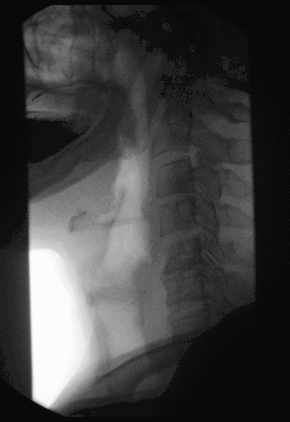

Fluoroscopy (/flʊəˈrɒskəpi/[1]) is an imaging technique that uses X-rays to obtain real-time moving images of the interior of an object. In its primary application of medical imaging, a fluoroscope (/ˈflʊərəskoʊp/)[2][3] allows a physician to see the internal structure and function of a patient, so that the pumping action of the heart or the motion of swallowing, for example, can be watched. This is useful for both diagnosis and therapy and occurs in general radiology, interventional radiology, and image-guided surgery.

In its simplest form, a fluoroscope consists of an X-ray source and a fluorescent screen, between which a patient is placed. However, since the 1950s most fluoroscopes have included X-ray image intensifiers and cameras as well, to improve the image's visibility and make it available on a remote display screen. For many decades, fluoroscopy tended to produce live pictures that were not recorded, but since the 1960s, as technology improved, recording and playback became the norm.

Fluoroscopy is similar to radiography and X-ray computed tomography (X-ray CT) in that it generates images using X-rays. The original difference was that radiography fixed still images on film whereas fluoroscopy provided live moving pictures that were not stored. However, today radiography, CT, and fluoroscopy are all digital imaging modes with image analysis software and data storage and retrieval.